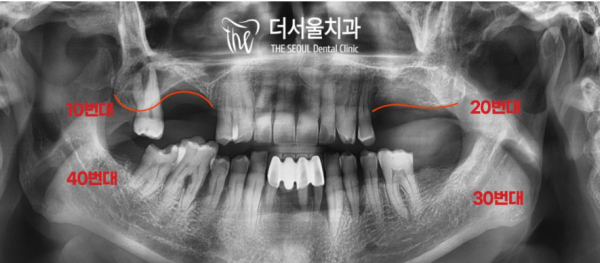

우선 정확한 진단을 위해 파노라마 사진을 찍어보기로 했습니다.

저희 태평역치과 더서울치과는 환자분의 정확한 진단을 통해 구체적인

치료 계획을 수립하여 안전하고 정확하게 치료를 해 드리고 있습니다!

골소실이 심하여 바로 수술이 불가하다는 결론입니다.

때문에 상악동거상술을 통해 뼈이식을 진행하여 모자란 골을 채워주기로합니다.

그 이후에 임플란트가 진행될예정입니다.